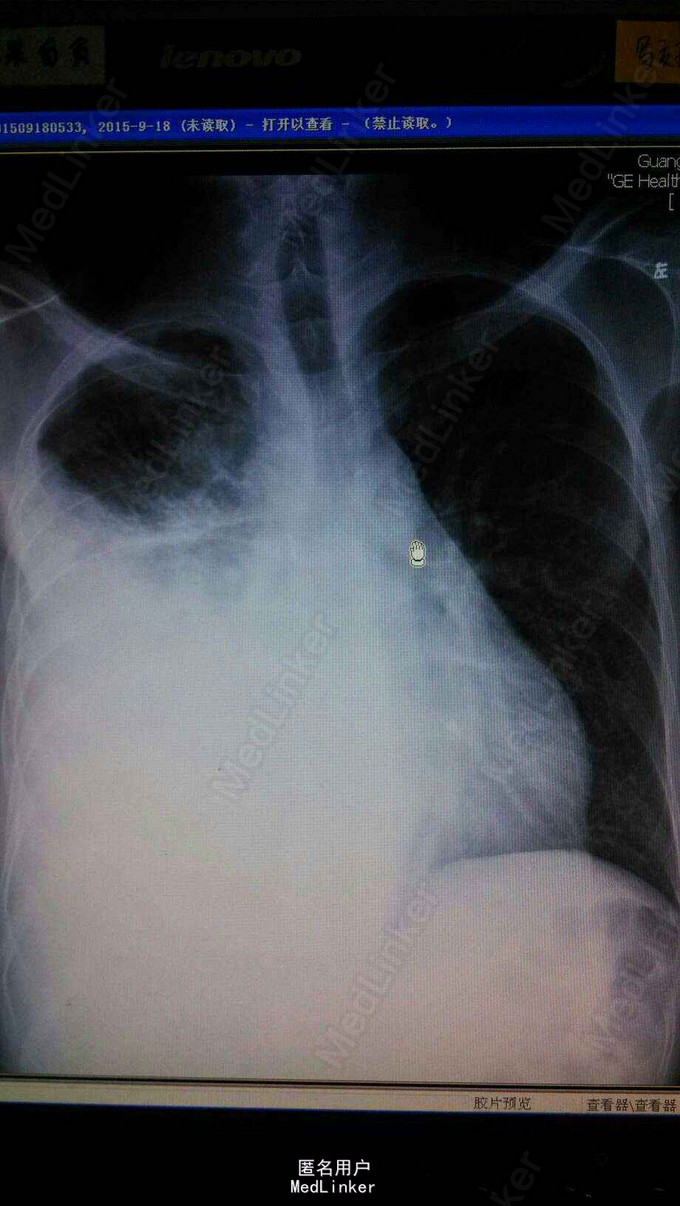

查体右下肺呼吸音减弱,无干湿罗音。心音正常。胸片示右胸膜增厚,少量积液。行胸膜活检示胸膜恶性间皮瘤。

患者治疗6周期后,因经济原因停止化疗。今年复查胸片示右肺大量实变,b超证实非胸水。考虑为肿瘤进展。胸膜间皮瘤往往以胸水为首发,易误诊漏诊,对反复胸水治疗效果欠佳者,应尽早应胸膜活检。胸膜间皮瘤最佳治疗方案是力比泰。